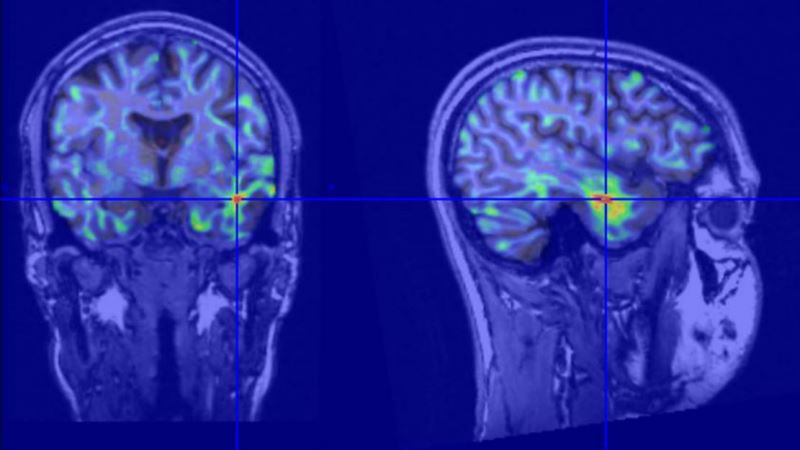

Sophisticated imaging technology that uses higher magnet strengths and computational tools allow Mayo Clinic doctors to identify where seizures originate within 1 millimeter. In the past, physicians may have been unable to identify the small lesions or abnormalities in the brain that caused their epilepsy.

Mayo Clinic teams supplement their surgical expertise with advanced robotic systems to enhance the surgical placement of spine instrumentation. Computed tomography (CT) or fluoroscopic imaging are used before and during surgery help determine the path used by the robot at every level of the spine.

Successful treatment starts with an accurate diagnosis. Whether you are newly diagnosed or if you’ve been living for years with a neurological disorder, Mayo's locations in Arizona, Florida and Minnesota use the latest diagnostic imaging to pinpoint the exact cause of your condition.